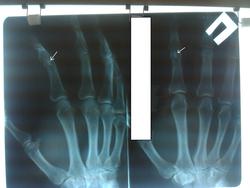

Пациент, 44 г. Направительный диагноз: ушиб 2 пальца. Что это может быть (указано стрелкой)

Эностоз

Или пишу локальный участок остеосклероза.

Это не эностоз, это норма.

Согласна, эностоз и еще, обычно имеется профессиональный анамнез - микротравмы.

Мелореостоз по эндостальному типу)

По таким снимкам не сказать точно, эностоз там или сесамовидная косточка прячется. Ведь возможно.